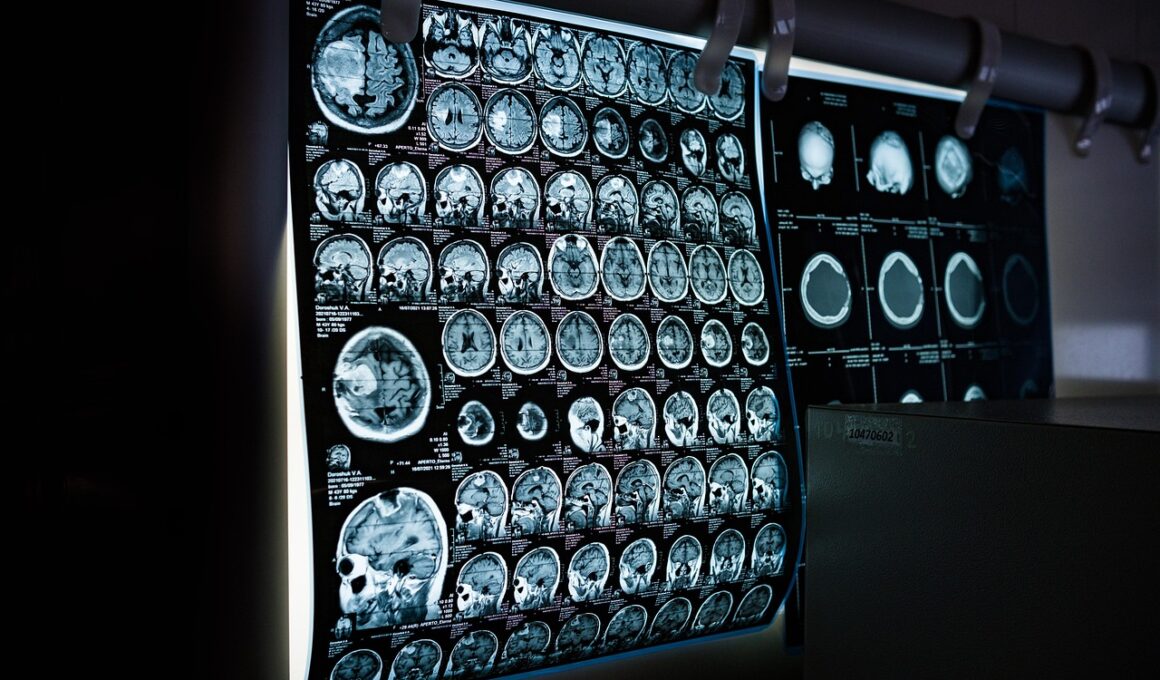

Clinical exercise testing is essential for assessing an individual’s physiological response to stress and determining their cardiovascular fitness. During these tests, imaging techniques enhance our understanding of how various systems in the body respond during exercise. These techniques comprise modalities like echocardiography, nuclear imaging, and MRI, which can visualize heart and lung activities under stress. Echocardiography allows for the evaluation of heart structure and function, while nuclear imaging assesses blood flow and overall myocardial perfusion. MRI provides detailed insights into cardiac muscle mechanics and can detect subtle ischemic changes during physical exertion. The integration of imaging into exercise tests allows clinicians to make more informed decisions regarding diagnosis and treatment. Furthermore, these imaging techniques help monitor the effectiveness of newly established exercise programs. The objective of this article is to explore the role of different imaging techniques during clinical exercise tests. Understanding the interplay of exercise and imaging not only advances clinical practices but also enhances patient outcomes, ensuring safer and more effective treatment strategies in exercise physiology. Thus, embracing modern imaging technologies in exercise testing is a paradigm shift that significantly benefits cardiovascular health monitoring.

Imaging techniques have evolved to support clinical exercise testing, significantly enhancing diagnostic accuracy. One of the most effective applications is echocardiography, which provides real-time imaging of heart functions and structures. During exercise, echocardiography assesses the heart’s size and contractility, revealing important changes attributed to increased workload. Reportedly, this can help clinicians determine whether cardiovascular performance matches the intensity of the exercise being conducted. Besides, nuclear imaging showcases how blood flows during physical activity in order to detect complications. This imaging modality allows medical professionals to observe vital processes in the heart and hemodynamic responses to physical stress while providing concrete data on the efficiency of blood circulation. Although traditionally performed under resting conditions, advancements now enable stress-induced imaging, reflecting real-world physiological responses. MRI, on the other hand, tracks advanced heart conditions such as cardiomyopathy alongside measuring precise cardiac function metrics. Together, these modalities represent a vital aspect of clinical practice, facilitating early intervention aimed at minimizing exercise-related risks. The inclusion of these techniques offers a comprehensive view, further emphasizing their indispensable role in evaluating patients during exercise.